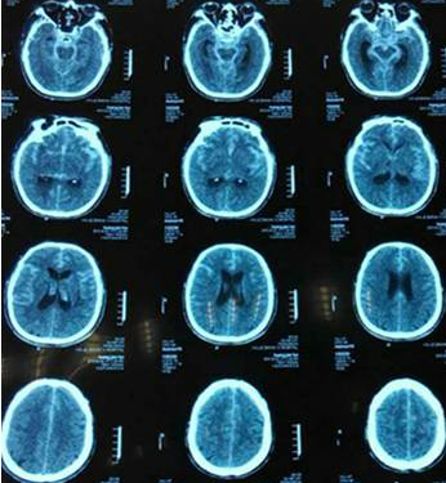

1.男70岁,Fisher 3级,H-H 3级,头CT:SAH。

3.既往高血压病史21年。

造影提示后交通大型动脉瘤,后交通和脉前动脉从瘤体上发出。

大型动脉瘤微导管瘤内成袢超选远端或瘤体上的分支是基本技术。

微导管瘤内解袢是相对应的技术,常用方法是把导丝退到动脉瘤开口以下,旋转导丝,缩小袢,同时下撤微导管,当看到微导管远端头部轻微前跳时说明瘤内袢解开,特殊解袢困难的可采用远端支架或球囊锚定技术。